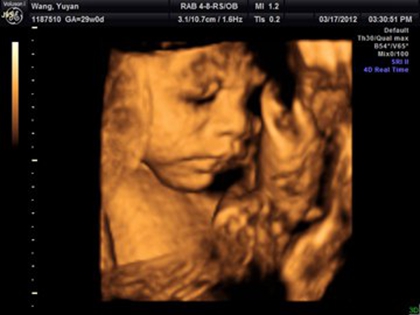

网上有一种说法是,在做四维彩超的时候,如果是女宝宝是比较不容易配合的,如果是男宝宝更容易通过,那么是不是四维女宝更容易配合呢,四维女宝特征有哪些?

四维女宝宝特征有哪些?